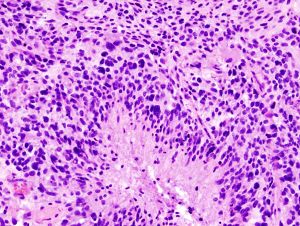

- جمع واختبار عينة من الأنسجة غير الطبيعية (خزعة): اعتمادًا على موقع الورم الدبقي، قد يتم إجراء خزعة باستخدام إبرة قبل العلاج أو كجزء من عملية لإزالة ورم الدماغ.

قد يتم إجراء خزعة باستخدام إبرة بالتوضيع التجسيمي للأورام الدبقية في المناطق التي يصعب الوصول إليها أو المناطق الحساسة جدًا داخل الدماغ التي قد تتضرر من أي عملية أكثر توسعًا. خلال خزعة إبرة التوضيع التجسيمي، يحفر جراح الأعصاب ثقبًا صغيرًا في الجمجمة. ثم يتم إدخال إبرة رفيعة من خلال ثقب. تتم إزالة الأنسجة من خلال الإبرة، والتي كثيرًا ما يتم توجيهها باستخدام التصوير المقطعي المحوسب أو المسح الضوئي بالتصوير بالرنين المغناطيسي. ثم يتم تحليل عينة الخزعة تحت المجهر لتحديد ما إذا كانت سرطانية أو حميدة.

تعد الخزعة هي الطريقة الوحيدة لتشخيص ورم الدماغ بشكل نهائي وإمدادك بتشخيص لتوجيه قرارات العلاج. واستنادًا إلى هذه المعلومات، يمكن لطبيب الأمراض تحديد درجة الورم في الدماغ أو مرحلته.

وتنقسم الأورام إلى أربع درجات حيث تكون أورام الدرجة الأولى الأبطأ نموًا وأكثرها خلايا حميدة وتحتوي أورام الدرجة الرابعة على أكثر الخلايا السرطانية شذوذًا وعنفًا.